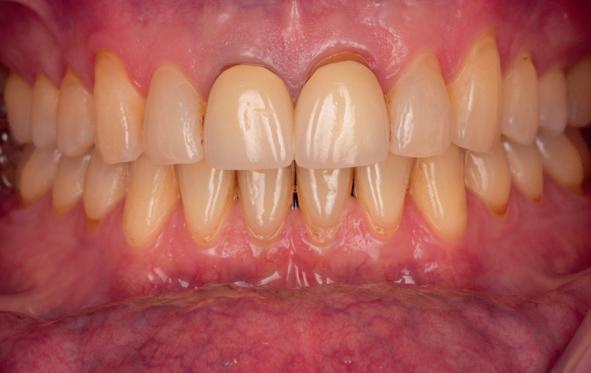

Esthetiek in de tandheelkunde, met name in het front, is een samenspel tussen de roze zachte weefsels en de witte harde weefsels. In het Engels wordt dit ook wel aangeduid met “pink and white esthetics”, waarbij het verkrijgen van correcte pink esthetics over het algemeen een grotere uitdaging vormt dan de white esthetics. Deze roze esthetiek is vooral van belang bij gebitselementen waarbij sprake is van recessie (het terugtrekken van de gingivalijn, waardoor de radix en een langere tand zichtbaar worden). De situatie wordt nog uitdagender wanneer een tand of kies niet is aangelegd, of in het verleden is verwijderd. Het element zorgt er immers voor dat de gingiva rondom de natuurlijke kroon ligt en dat er voldoende weefseldikte rondom deze kroon aanwezig is. Als het element ontbreekt, groeit het alveolaire bot dicht, omdat er geen radix meer is, en daarmee ook de mucosa (wanneer er geen element meer aanwezig is, spreken we niet meer van gingiva maar van mucosa), die dan afgevlakt is. De papillen tussen de afwezige elementen vlakken dan ook af.

Om één of meer afwezige elementen te herstellen bij een vaste voorziening, kan er een etsbrug of kunnen er implantaten worden geplaatst. De esthetiek valt of staat hierbij met de aanvulling van de zachte weefsels, zowel in de vorm van verbreding hiervan als het creëren van een zogenoemd emergence profile –dat wil zeggen dat de tand op een natuurlijk ogende wijze vanuit het tandvlees tevoorschijn moet komen.

tinaal geslepen te worden als er geen 1,5 mm ruimte voor de vleugels behaald kan worden. De ruimte was op de dunste plekken 1 mm, dus een kleine preparatie in de 12 en 22 palatinaal was nodig. Omdat de kaak volledig afgevlakt was en dun was geworden, kunnen de dummies van de etsbrug enkel op de kaak “gelegd worden”, maar daarbij zijn er geen papillen en staat de cervicale rand van de dummies net voor de kaak. Een esthetisch resultaat kan daarmee niet behaald worden. Daarom is een aanvulling van de zachte weefsels in de breedte nodig, als het creëren van een emergence profile, waarbij het oogst alsof de gebitselementen uit het weefsel vertrekken.

5. Beginsituatie voor behandeling